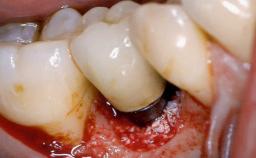

Paolo Casentini demonstrates that peri-implantitis can be successfully treated even at an advanced stage. He discusses a case in which the existing implants and prostheses were both retained while regenerating the defect and creating a band of keratinized tissue. A 69-year-old female patient was referred by her general dentist for evaluation of a recurrent infection at previously placed and restored implants in the posterior left mandible. The patient’s chief complaint was recurrent swelling and pain in the molar region of the left posterior mandible with discomfort during brushing in the same area. The patient reported receiving two implants (36 and 37) nine years earlier.